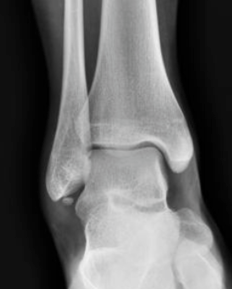

What is this?

What is the epidemiology and pathoanatomy of Os Subfibulare?

What are the symptoms and signs of Os Subfibulare?

What imaging is helpful in Os Subfibulare?

What is DDX of Os Subfibulare?

What is the Tx of Os Subfibulare?